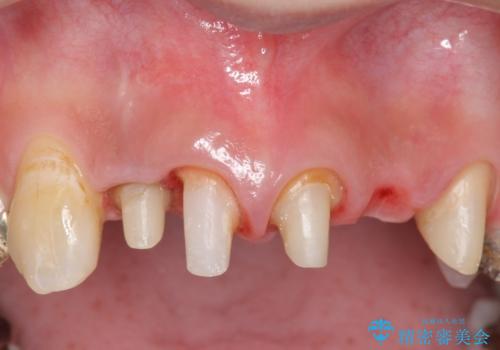

- 昔入れた被せ物と歯茎の間の隙間が気になると来院された方の症例です。

右上1、2番目の歯と左上1、2、3、番目の歯のブリッジを除去し、オールセラミッククラウンによる補綴を行うことで見た目を改善しました。